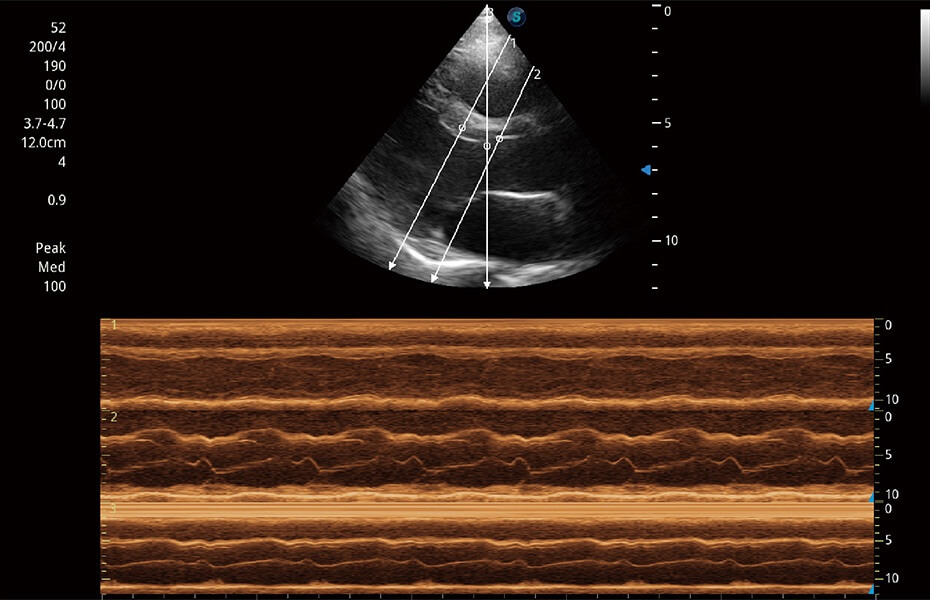

ProPet 60 作為一款高端臺式動物超聲設(shè)備,為動物醫(yī)生的日常診斷提供了一系列貼合動物臨床需求、解決臨床實(shí)際問題的高級成像功能。憑借全系列高清探頭,滿足醫(yī)生對腹部、心臟、生殖、淺表、肌骨等成像的所有需求,切實(shí)幫助您提升檢查效率,提高診斷信心。